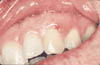

Fig 1a: Preoperative view of graft recipient site.

In my practice, I use cyanoacrylate to facilitate the free gingival graft surgical procedure (Fig. 1(a)). Following preparation of the recipient site, the donor tissue is obtained from the palate. Cyanoacrylate is then applied as a dressing over the donor site. The material is useful here because of its hemostatic and bacteriostatic properties and because it acts as a protective barrier during the healing phase (Fig. 1(b)).